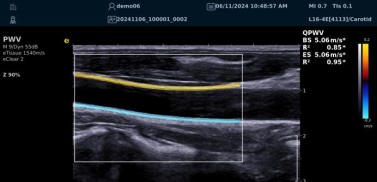

QPWV 彩色脉搏波传导速度定量技术

QPWV 技术是银河官网医疗的极速脉搏波速度测量技术,对脑卒中诊疗优势明显:

image.png

? 可进行动脉壁运动速度 - 时间彩色成像,直接测量单点脉搏波传导速度及相关参数(如 BSES 时的速度及标准差)。

? 能在血管内中膜增厚前的内皮功能不全阶段检测异常,对早期动脉硬化评估极具临床价值。

? 操作简单直接,无需附加设备,影响因素少,检测快速、重复性和稳定性高。